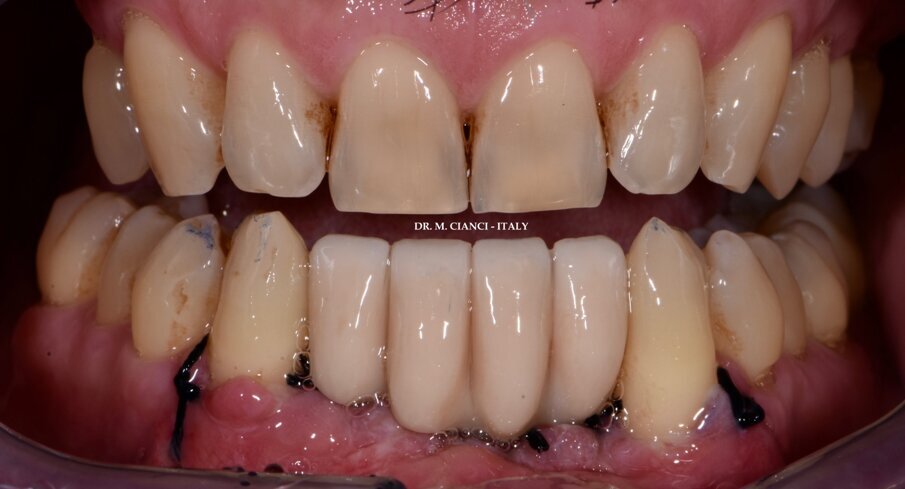

Completata la sutura, avvitati 3 Scan Body sui Multi-Im in pochi minuti abbiamo eseguito la scansione digitale intra-orale 3Shape inviandola con un clic al laboratorio odontotecnico il quale ha elaborato, progettato e stampato in 3D la protesi provvisoria in PMMA avvitata con interfaccia estetica su impianti (Fig. 12) da consegnare al paziente tre ore dopo la chirurgia (Fig. 13).

Fig. 13 - Ponte provvisorio avvitato per il carico immediato.